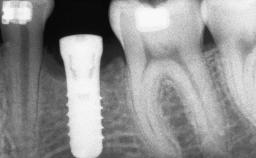

A 47-year-old Caucasian woman with a single-tooth edentulous space at the site of the left maxillary canine was referred for treatment. She had undergone traumatic extraction of this impacted canine several months before referral. Her chief complaint was the dissatisfying appearance of her smile. The patient desired a stable and esthetic rehabilitation of the site. Her dental history showed no evidence of periodontal disease or bruxism. She had no systemic diseases, was not taking any medications, and did not smoke. The extraoral examination revealed a high lip line and an inadequate soft-tissue volume at the defective canine site. Large black triangles were visible between the canine and its adjacent teeth.

Bone Augmentation Staged|Vertical

Augmentation Materials Autogenous chips|Membrane

Bone Volume Deficient vertically or deficient vertically AND horizontally